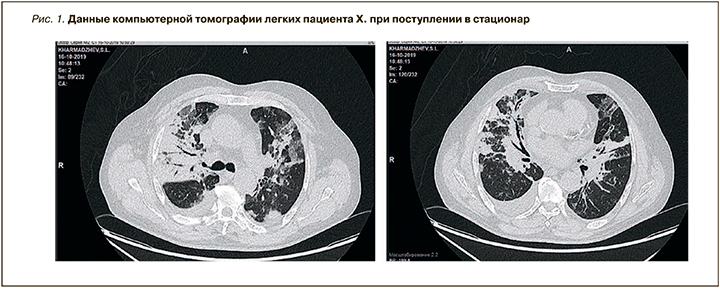

При анализе лабораторных исследований обратила на себя внимание выраженная лимфопения, лейкоцитарный сдвиг влево, увеличение скорости оседания эритроцитов (СОЭ) в 5 раз, увеличение D-димеров в 10 раз (табл. 1). Также мы зафиксировали признаки почечной недостаточности – повышение уровня креатинина более 200 мкмоль/л (табл. 2).

При компьютерной томографии (КТ) органов грудной клетки обнаружена картина двусторонней полисегментарной пневмонии (субтотальная справа). Очаги поражения ткани легкого выглядели как очаги затемнения в виде «матового стекла». В правой плевральной полости присутствовал выпот с компрессией правого легкого, также визуализировались следы выпота в левой плевральной полости. Лимфаденопатия средостения. Легочная гипертензия. Признаков тромбоэмболии легочной артерии (ТЭЛА) по данным КТ органов грудной клетки обнаружено не было, однако отмечалось повышение уровня D-димера (рис. 1).